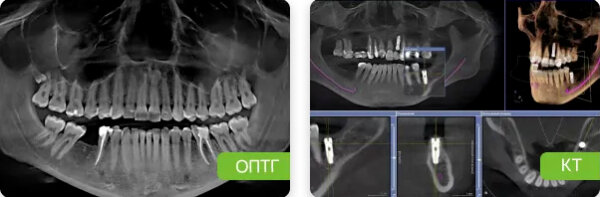

Рентгенологические исследования. Компьютерная томография – самый точный и информативный метод исследования при пародонтите, позволяет точно определить распространение пародонтальных карманов, их глубину и ширину. Дополнительно делаются ортопантомограмма и прицельные снимки.